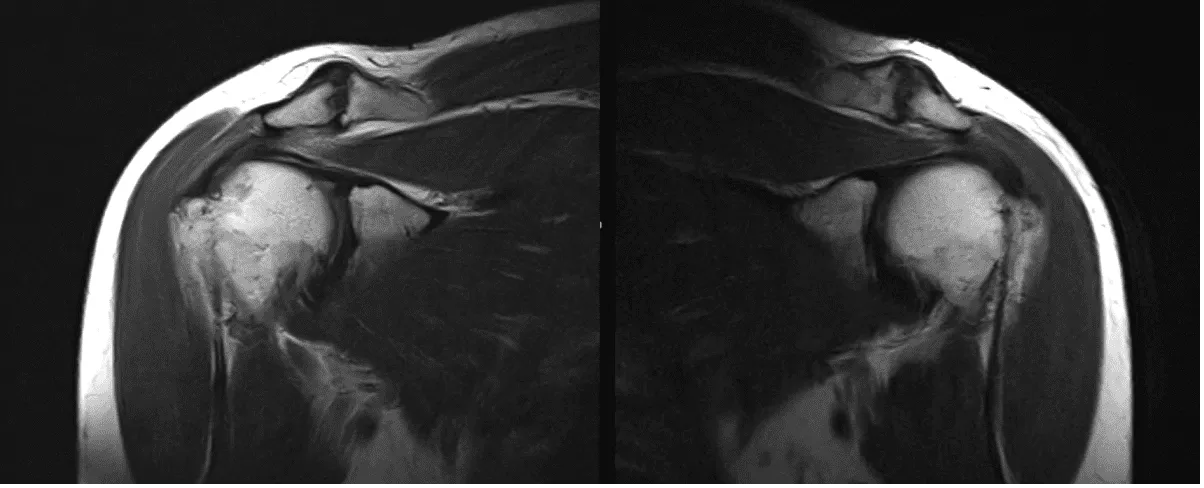

A 50-year-old patient was in our office with complaints regarding bilateral shoulder pain and neck and upper back pain. She has a history of neck injury. For aggravating factors, lifting, pushing/pulling, and throwing.

The patient presented MRI results for both shoulders. For the right, low-grade interstitial tear of the posterior supraspinatus tendon. Mild supraspinatus and subscapularis tendinosis.

For the left, A low grade interstitial tear of the posterior supraspinatus tendon on mild background tendinosis. Tearing of the posterior-superior labrum. Mild acromioclavicular joint osteoarthritis.

MRI Left Shoulder Non-contrast